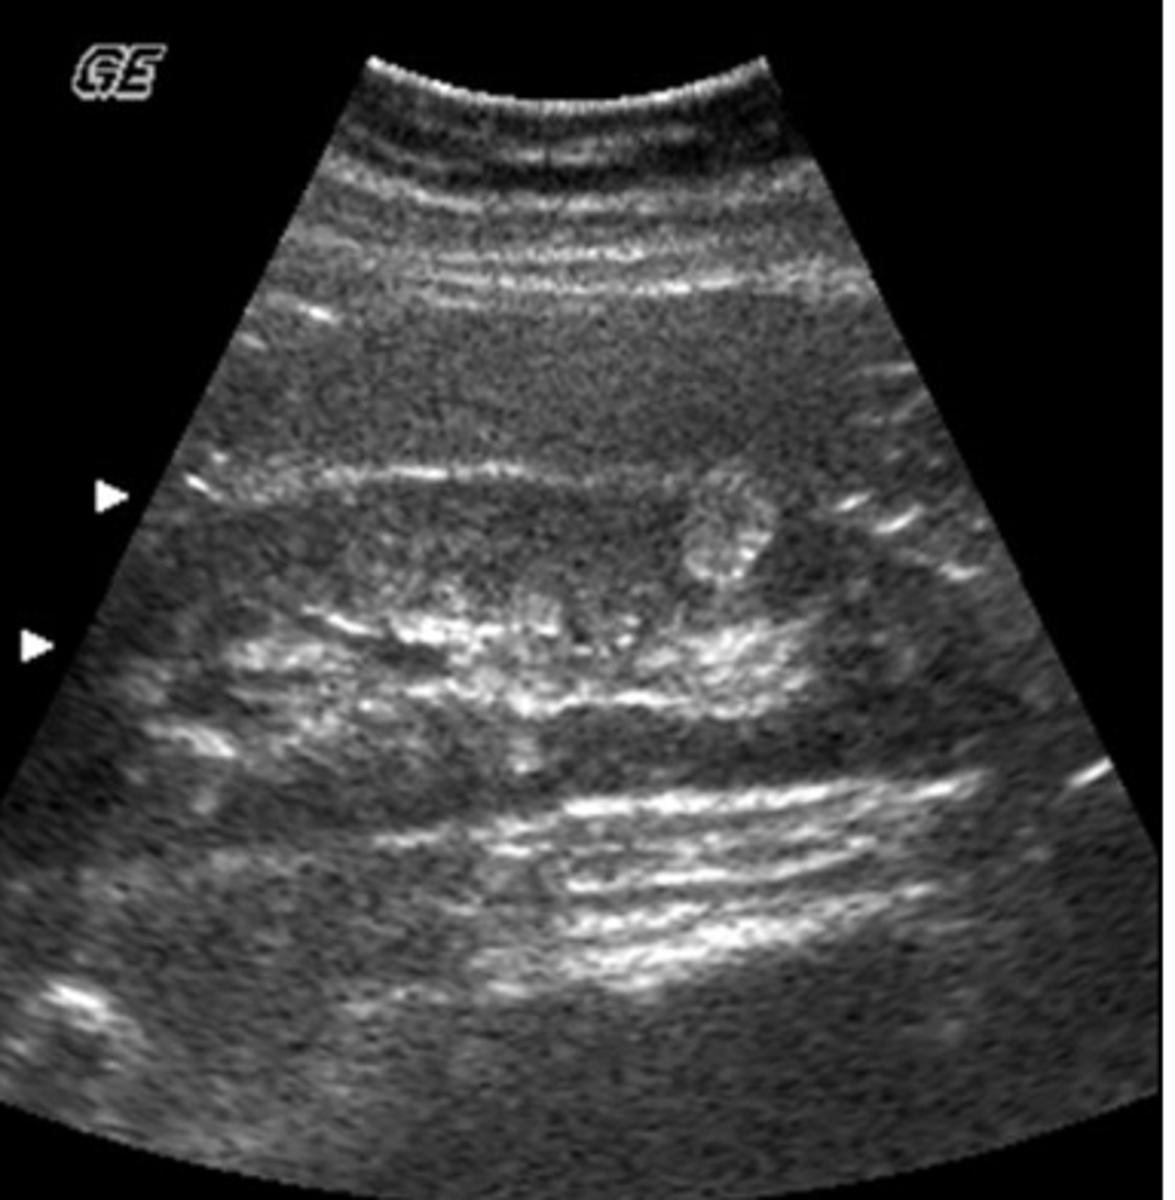

b. splenic and retroperitoneal varices

A 49-year-old male presented with a clinical history of liver cirrhosis and portal hypertension. In the transverse image below, multiple hypoechoic structures are seen at the splenic hilum and between the kidney and spleen. What is the most likely etiology of these structures.

a. multiple aneurysms of the splenic artery

c. loculated ascites

d. polycystic kidney disease

e. fluid-filled loops of bowel

c. search for the presence of portosystemic collaterals

You are performing an ultrasound exam in a patient with a history of alcoholic liver cirrhosis. You have documented the presence of splenomegaly and dilated veins at the splenic hilum. Considering the patient's history and findings, what else should you look for?

a. search for signs of acute cholecystitis

b. carefully scan the spleen for presence of infarcts

d. check the pelvis for a left side mass

e. rule out the presence of an aortic aneurysm